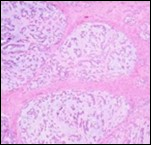

Parachordoma morphologically simulates a chordoma although tumour countenance is variable. Grossly, parachordoma depicts a firm, lobulated or nodular appearance, variable magnitude of 2 centimetres to 8 centimetres with a mean diameter of 3.5 centimetres. Tumour perimeter is well defined. Cut surface is greyish/ white, gelatinous, semi-translucent with cartilaginous zones and disseminated foci of myxoid material 5. Necrosis and haemorrhage may be absent although enlarged neoplasms are associated with focal haemorrhage, necrosis and cystic degeneration. Cogent tissue specimen obtained exhibits a tumour composed of nests and cords of cells with eosinophilic, clear, vacuolated cytoplasm and uniform, spherical to elliptical, hyperchromatic or bland nuclei. The neoplasm displays a reticular or trabecular pattern of evolution, intermingled with foci of myxoid, cartilaginous or hyalinised matrix.

Microscopically, a well circumscribed, un-encapsulated, multinodular neoplasm comprised of spheroidal, epithelioid or plump spindle- shaped cells is denominated with tumour cells configuring clusters, chains, nodules and whorls although a glandular architecture is typically absent. An encompassing chondromyxoid, hyaline stroma is discerned and the tumour is traversed with fibrous tissue septa 5, 6.

Three distinct cellular subtypes constitute a parachordoma. Epithelioid cells, miniature glomoid cells and spindle-shaped cells. Besides, the neoplasm has a distinctive population of cells with vacuolated cytoplasm, simulating physaliferous cells of chordoma 5.

Parachordoma is composed of aggregates, whorls and a pseudo-glandular pattern of spheroidal cells embedded within a focally myxoid, hyaline stroma, subdivided by broad, fibrous tissue septa. Foci of fresh and old haemorrhage are exemplified. Tumour necrosis or vascular invasion is usually absent. Mitotic activity is minimal and usually below < one mitosis per 20 high power fields5, 6.

Multinodular tumour architecture is constituted by miniature, uniform, elliptical or spindle-shaped cells with scanty, eosinophilic, finely vacuolated cytoplasm and miniature, regular or hyperchromatic nuclei. Myxoid tumour matrix is envelops neoplastic cells configuring cords and strands. Nuclear pleomorphism is absent. Tiny foci of necrosis with focal chondroid differentiation may ensue6. Meningo-endothelial cells, physaliferous cells, rhabdoid cells, ductal differentiation and anaplastic cellular dedifferentiation is usually absent. Myoepithelial carcinoma displays nuclear atypia, elevated mitotic rate and extensive foci of tumour necrosis5. Figure 1, Figure 2, Figure 3, Figure 4, Figure 5, Figure 6, Figure 7, Figure 8.

Figure 1.Parachordoma on fine needle aspiration cytology depicting clusters of spheroidal cells with eosinophilic cytoplasm, regular nuclei and clumped, encompassing myxoid stroma 13.